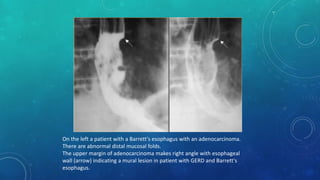

On the left a patient with a Barrett's esophagus with an adenocarcinoma.

There are abnormal distal mucosal folds.

The upper margin of adenocarcinoma makes right angle with esophageal

wall (arrow) indicating a mural lesion in patient with GERD and Barrett's

esophagus.